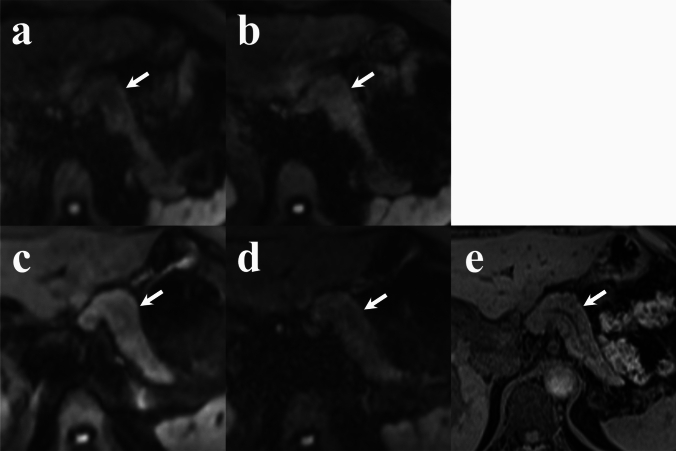

{"title":"Improvement of image quality of diffusion-weighted imaging (DWI) with deep learning reconstruction of the pancreas: comparison with respiratory-gated conventional DWI.","authors":"Kazuki Oyama, Fumihito Ichinohe, Yasuo Adachi, Yoshihiro Kito, Katsuya Maruyama, Minoru Mitsuda, Thomas Benkert, Omar Darwish, Yasunari Fujinaga","doi":"10.1007/s11604-025-01790-w","DOIUrl":null,"url":null,"abstract":"<p><strong>Purpose: </strong>This study aimed to evaluate the efficacy of deep learning-based reconstruction (DLR) in improving pancreatic diffusion-weighted imaging (DWI) quality.</p><p><strong>Materials and methods: </strong>In total, 117 patients (mean age of 68.0 ± 12.9 years) suspected of pancreatic diseases underwent magnetic resonance imaging (MRI) between July and December 2023. MRI sequences included respiratory-gated conventional diffusion-weighted images (RGC-DWIs), respiratory-gated diffusion-weighted images with deep learning-based reconstruction (DLR) (RGDLR-DWIs), and breath-hold diffusion-weighted images with DLR (BHDLR-DWIs) (short TE and long TE equal to other DWIs) at a 3 T MR system. Among these patients, 27 had solid lesions. Two radiologists qualitatively assessed pancreatic shape, main pancreatic duct (MPD) visualization, and solid lesion conspicuity using a 5-point scale. Quantitative analysis included apparent diffusion coefficient (ADC) values for pancreatic parenchyma and solid lesions, signal-to-noise ratio (SNR), pancreas-to-muscle signal-intensity ratio (PM-SIR) and lesion-to-pancreas signal-intensity ratio (LP-SIR). Differences among DWI sequences were analyzed using Friedman's and Bonferroni's tests.</p><p><strong>Results: </strong>Qualitatively, BHDLR-DWIs (short TE) had the highest scores for pancreatic shape and MPD but lowest for solid lesions visibility, whereas RGDLR-DWIs had the highest score for solid lesions. Quantitatively, BHDLR-DWIs (short TE) had the lowest ADC values for pancreatic parenchyma and solid lesions, with the highest PM-SIR. There was no significant difference between BHDLR-DWIs (short TE) and RGDLR-DWIs for solid lesion ADC values. RGC-DWIs had the highest SNR, though differences from RGDLR-DWIs and BHDLR-DWIs (short TE) were not significant. Although LP-SIR in RGDLR-DWIs were the lowest, the difference was not significant.</p><p><strong>Conclusion: </strong>BHDLR-DWIs (short TE) provided the best pancreatic morphology image quality, whereas RGDLR-DWIs were superior for solid lesion detection.</p>","PeriodicalId":14691,"journal":{"name":"Japanese Journal of Radiology","volume":" ","pages":"1509-1519"},"PeriodicalIF":2.1000,"publicationDate":"2025-09-01","publicationTypes":"Journal Article","fieldsOfStudy":null,"isOpenAccess":false,"openAccessPdf":"https://www.ncbi.nlm.nih.gov/pmc/articles/PMC12396992/pdf/","citationCount":"0","resultStr":null,"platform":"Semanticscholar","paperid":null,"PeriodicalName":"Japanese Journal of Radiology","FirstCategoryId":"3","ListUrlMain":"https://doi.org/10.1007/s11604-025-01790-w","RegionNum":4,"RegionCategory":"医学","ArticlePicture":[],"TitleCN":null,"AbstractTextCN":null,"PMCID":null,"EPubDate":"2025/4/26 0:00:00","PubModel":"Epub","JCR":"","JCRName":"","Score":null,"Total":0}

Results: Qualitatively, BHDLR-DWIs (short TE) had the highest scores for pancreatic shape and MPD but lowest for solid lesions visibility, whereas RGDLR-DWIs had the highest score for solid lesions. Quantitatively, BHDLR-DWIs (short TE) had the lowest ADC values for pancreatic parenchyma and solid lesions, with the highest PM-SIR. There was no significant difference between BHDLR-DWIs (short TE) and RGDLR-DWIs for solid lesion ADC values. RGC-DWIs had the highest SNR, though differences from RGDLR-DWIs and BHDLR-DWIs (short TE) were not significant. Although LP-SIR in RGDLR-DWIs were the lowest, the difference was not significant.

Conclusion: BHDLR-DWIs (short TE) provided the best pancreatic morphology image quality, whereas RGDLR-DWIs were superior for solid lesion detection.